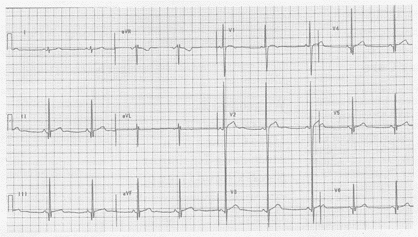

Figure. A 12-lead ECG obtained from a 21-year-old athlete.

Clinical Scenario: The 12-lead ECG shown in the Figure was obtained from a 21-year-old endurance-sport male athlete. What important cardiac abnormality might be present? What else might this ECG be reflective of?

Interpretation: The ECG in the Figure is not a normal tracing. There is sinus bradycardia and arrhythmia, normal intervals (PR, QRS, and QT), and a vertical though still normal mean QRS axis of approximately +90°. The findings of concern are several: 1) moderately deep (though narrow) Q waves in multiple leads (II, III, aVF, V3-V6); 2) markedly increased QRS amplitude (deep S waves in leads V1-V2, and early transition with tall R waves in leads V2-V4); and 3) the suggestion of prominent septal forces (tall R wave = S in lead V1, early transition, and the inferolateral Q waves just noted). In addition, there are some ST-T wave changes consistent with an early repolarization pattern (slight J point ST segment elevation in the inferolateral leads, and ST segment coving in leads V1-V4).

ECG abnormalities are commonly seen in otherwise healthy young adults. This is especially true in athletes. A recent study by Pelliccia and colleagues is particularly insightful with regard to the incidence of ECG abnormalities in young adult athletes and the clinical relevance of the abnormalities found (Pelliccia A, et al. Circulation. 2000; 102:278-284). Among a series of more than 1000 consecutive young Italian men and women participating in 38 different sporting activities, 60% had a normal or near normal tracing (early repolarization, 1° AV block and incomplete right bundle branch block were all considered near normal and acceptable normal variants in these otherwise healthy young adult athletes). Forty percent of the overall group had at least mild-to-moderate ECG abnormalities, of which approximately one third had distinctly abnormal tracings. Marked abnormalities were significantly more common in male athletes, athletes younger than 20 years of age, and in those participating in endurance sports (rowing, cycling, cross-country skiing, or long-distance running). Surprisingly, despite even striking ECG abnormalities, structural abnormality (beyond modest physiologic increase in selected cardiac dimensions on echocardiography) was uncommon. The "good" news derived from this study is that the ECG finding of a normal ECG in a young competitive athlete is highly predictive of a normal heart. The problematic result is that as many as 15% of young adult athletes (especially those involved in endurance sports) may have a markedly abnormal ECG, such as the one shown in the Figure. While echocardiography is appropriate (to rule out hypertrophic cardiomyopathy) in individuals such as the 21-year-old athlete in this case, the overwhelming majority of young competitive athletes with distinctly "abnormal" ECGs will end up having a structurally normal heart.